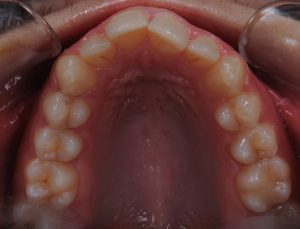

Maloclusión

Se caracteriza por una alineación incorrecta de los dientes, donde los dientes superiores e inferiores están en una relación normal, pero hay una falta de espacio que provoca que los dientes se solapen o estén apiñados.

Este problema puede generar dificultad para mantener una correcta higiene dental y afectar la estética de la sonrisa

INITIAL

22 Semanas de Tratamiento